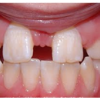

Hambatraumad

Põhimõtted – Trauma tagajärjel irdunud jäävhammast tasub alati tagasi istutada, kui õnnetuses on hammas ja alveool terveks jäänud. Kui ka hammas hiljem kaotataks, on istutamine tähtis, sest see kergendab implanteerimist...